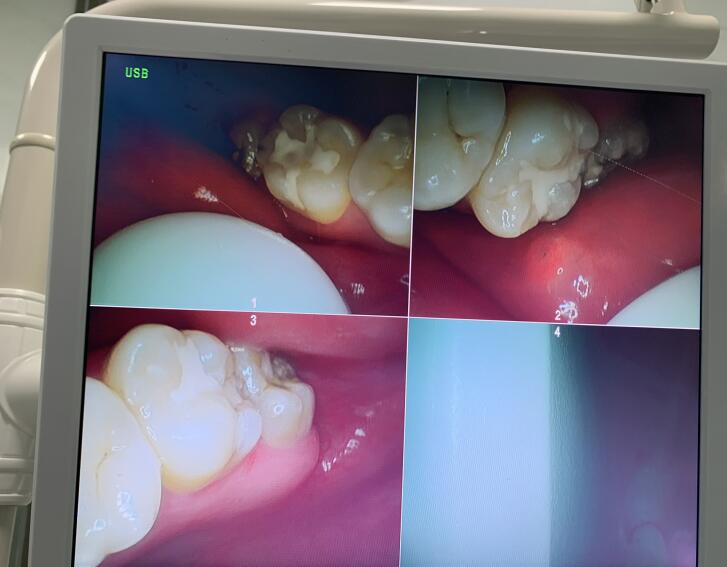

下面我直接给你们看看我补好的牙齿吧,填充的是树脂,没补好之前的是黑色的,就不放图了

一共有四颗被蛀虫咬空的牙齿,里面全是洞,把牙上面黑色的东西磨掉了,然后再补上了感觉舒服多了